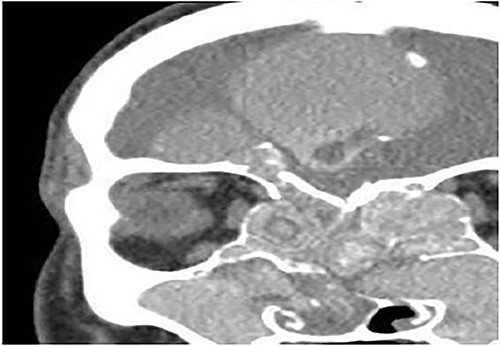

Case 6 (extensive into intraorbital and intracranial structures)

A 15-years-old male presented with bilateral nasal obstruction for a long time associated with nasal discharge, allergic nasal symptoms and headache. Endoscopic nasal examination revealed bilateral extensive nasal polyposis and mucin. CT scan (Fig. 7) and magnetic resonance imaging (MRI) scan (Fig. 8) of the paranasal sinuses confirmed the diagnosis of extensive bilateral allergic fungal pansinusitis with intraorbital and intracranial extradural extension. The patient underwent FESS, and all the polyps, mucin and fungal debris were removed from the sinuses. The patient continued on medical treatment and remained symptoms-free for 5 years follow-up.

Coronal CT paranasal sinuses shows heterogeneous opacities of the ethmoid and maxillary sinuses bilaterally. It is associated with complete opacification and extension through the widened ostiomeatal complex, obliterating the nasal cavities with polyposis. The ethmoid sinuses show expansion with lateral displacement and partial dehiscence of the lamina papyracea bilaterally. The roof of the right ethmoid sinus shows dehiscence with intracranial extension.